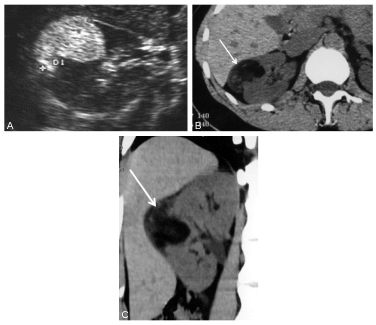

L’angiomyolipome est la tumeur bénigne la plus fréquente (figure 31.3) : son diagnostic repose sur la mise en évidence de graisse au sein de la tumeur :

- hyperéchogène par rapport au rein en échographie (non spécifique) ;

- avec une densité négative en scanner (entre – 100 et – 20 UH), signe spécifique qui permet d’affirmer le diagnostic.

Fig. 31.3 Angiomyolipome rénal droit.

Échographie (A) montrant une masse hyperéchogène compatible avec un contenu graisseux (non spécifique). Scanner sans injection en coupe axiale (B) et en reconstruction coronale (C) montrant que la masse (flèches) présente une densité graisseuse (– 75 UH) voisine de celle de la graisse périrénale.

Source : CERF, CNEBMN, 2022.